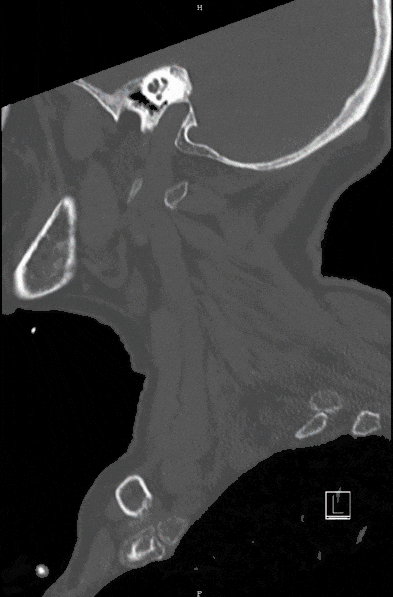

Spinal Injuries

Spinal column injuries can not only lead to fractures, thus instability, but thereby threaten the spinal cord and nerves in particular. The spinal cord syndrome is one of the most severe injuries and can lead to paralysis, sensory disturbances as well as bladder and rectal emptying disorders and even respiratory disturbances.